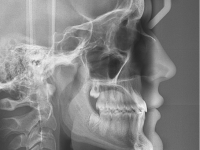

El paciente E.A. acude a nuestra consulta por diastema inferior y ausencia de contactos en los sectores laterales.

Chica de 17 años tratada en 1 año con stripping en los dientes inferiores